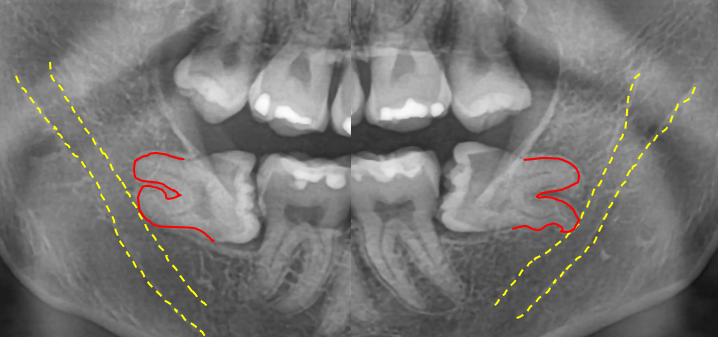

위쪽은 똑바로 나있었지만 아래 사랑니가 모두 매복 되었고 뿌리가 두 갈래로 갈라져 있었으며, 끝이 많이 휘어 있는 형태였어요.

또, 뿌리 끝과 하치조신경관의 거리가 매우 가까웠는데요.

이런 경우, 발치하다가 하치조신경관이 손상되는 경우도 있어서 매우 조심해야 됩니다.

이 케이스에서 가장 중요한 건 '뿌리를 부러뜨리지 않는 것'이었어요.

뿌리가 부러진다면... 부러진 끝부분을 찾기 위해 여기저기 만져보다가 오히려 신경관을 손상시킬 수도 있거든요.

잇몸을 가능한 적게 절개한 뒤, 필요한 만큼만 골 삭제를 하고 치아를 여러 조각으로 나눠 제거하는 계획을 세웠어요.